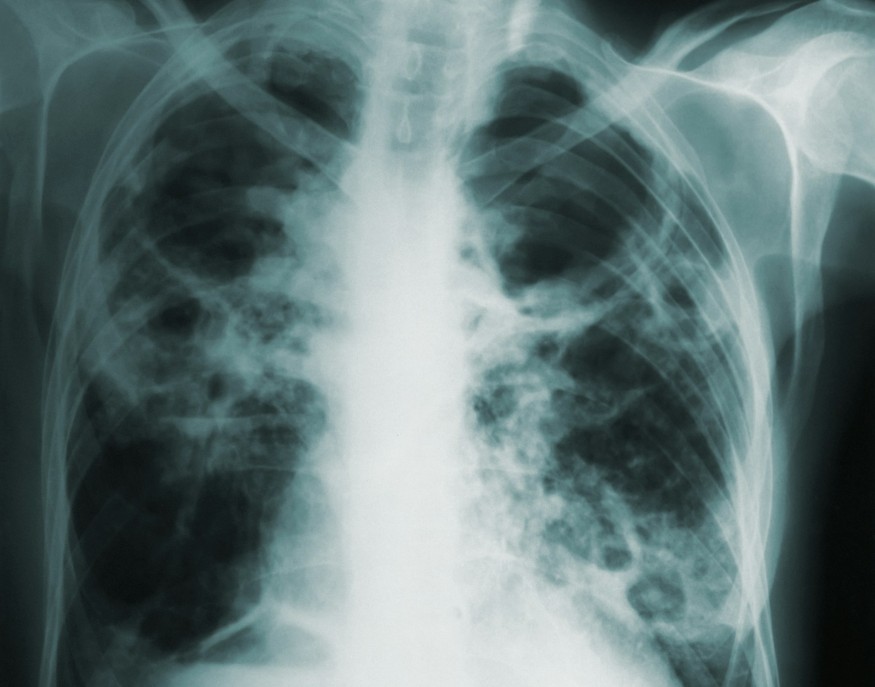

Public Health Wales has welcomed plans for a national lung screening programme, which will enable earlier diagnosis and treatment of cancers and ultimately save lives.

The Welsh Government’s decision to introduce screening for current and former smokers aged 55-74 comes after advice it received in March from Public Health Wales.

“Lung cancer is the leading cause of cancer death in Wales. Too often it is diagnosed late because it may not cause symptoms in its early stages. Screening gives us a chance to find it early, before symptoms appear.